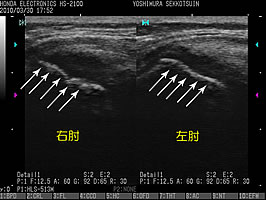

肘関節軽度屈曲位での内側短軸走査(↑)

右肘関節の画像特徴

・白矢印の先は不整(凸凹している)。

・青色の間隔が、左肘よりも右肘のほうが開いている。

・赤矢印先の低エコー域(黒い部分)が広い。